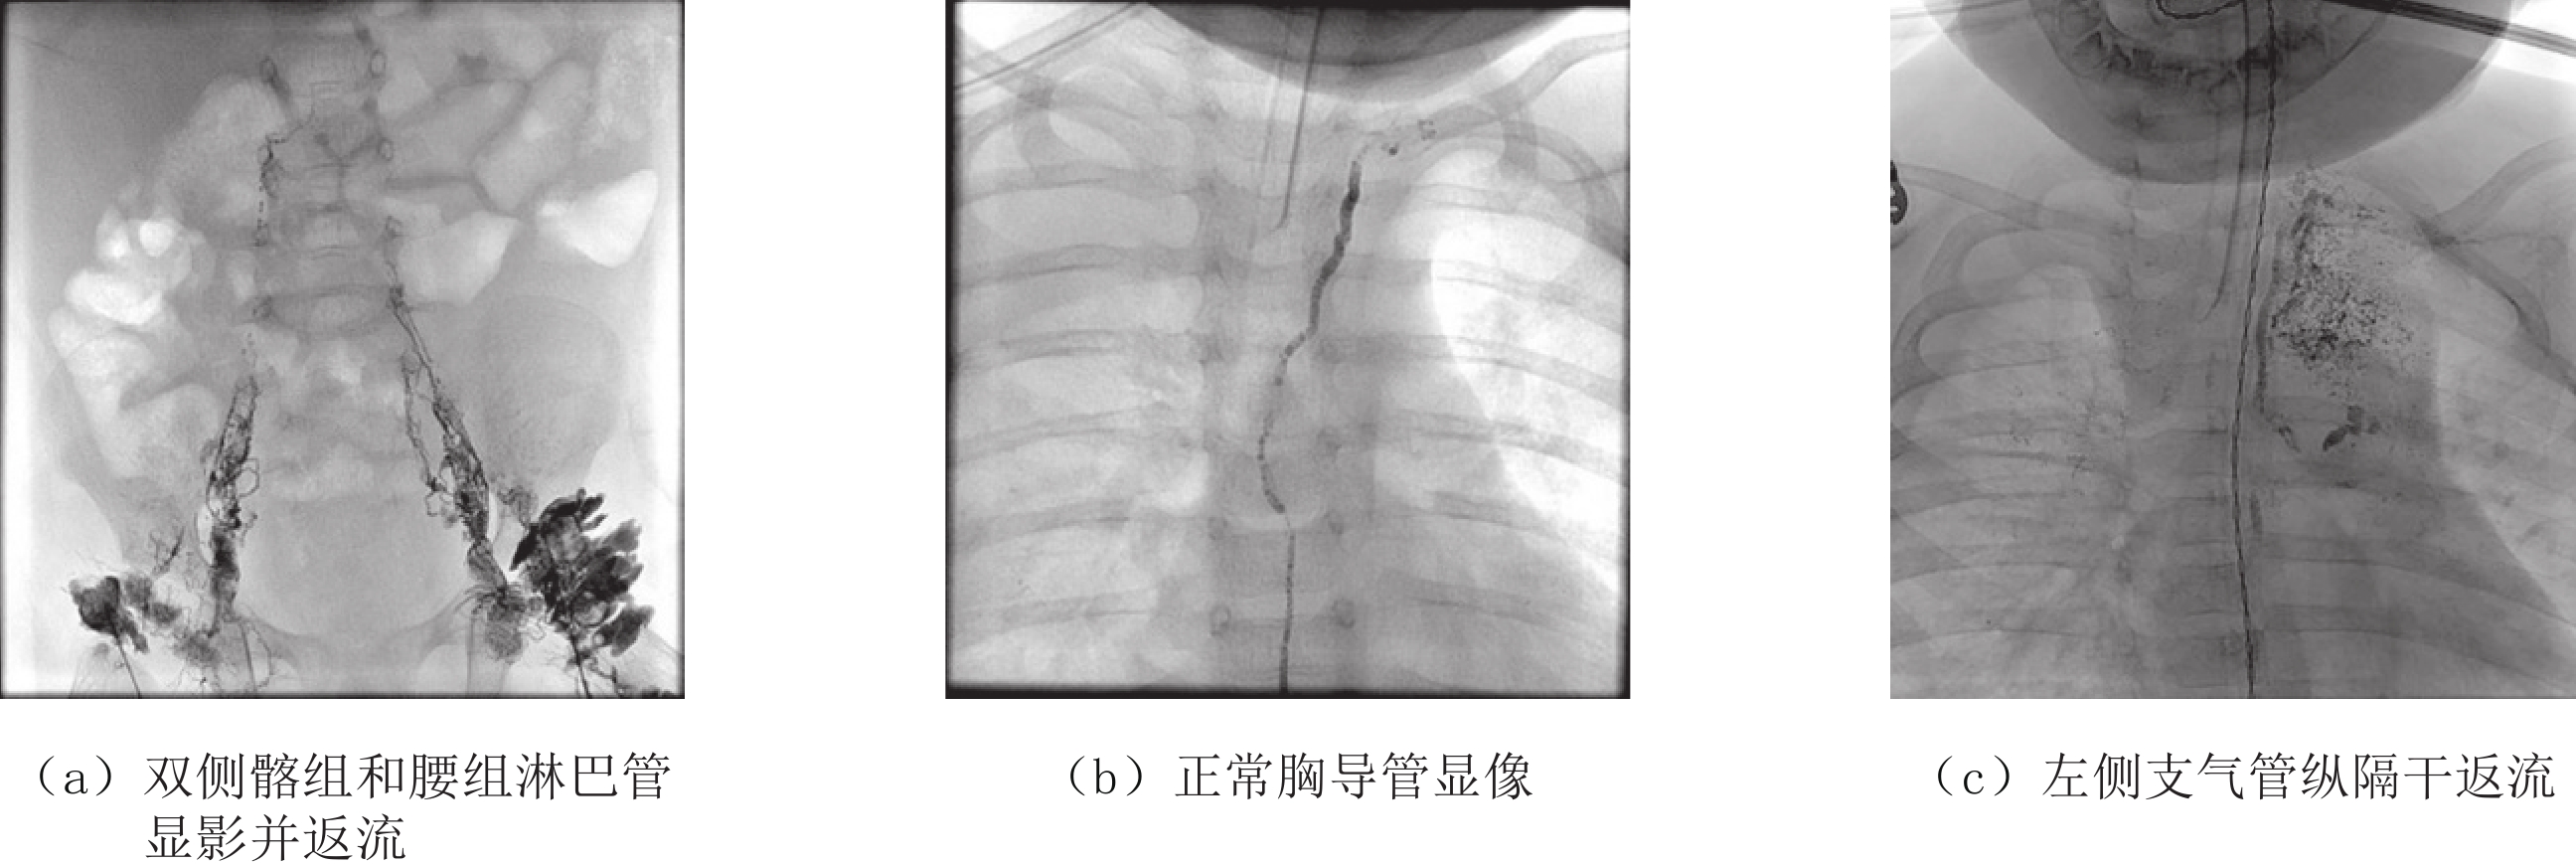

DLG是一种动态的影像观察过程,通过显示对比剂在淋巴管内的回流状况以及有无梗阻、返流、堆积或漏出等改变,有助于判断淋巴管的形态解剖、内部结构、功能状态及病变部位和类型。DLG涉及的相关技术指标包括对比剂、注射方式、X线动态摄影和信息记录等。

(3)X线动态摄影。对比剂注射成功后,随即在数字平板血管造影系统的透视模式下分时段动态观察淋巴系统显影情况并连续采集图像。正常情况下,对比剂自足背淋巴管流至胸导管末端的时间为20~30 min,所以应依据不同部位(下肢、盆腔、腹部、胸部和胸导管末端等)自下而上每间隔5~10 min进行动态透视和摄影。异常情况下的延迟时间差异较大,可长达60~360 min或更久或对比剂因梗阻无法进入胸导管内。

(4)信息记录。通过动态观察对比剂在淋巴管的流动情况,记录如下信息:①对比剂的流速,即到达某特定部位的时间或单位时间所到达的部位;②异常部位内显影淋巴管的数量和管径;③对比剂的分布特征;④显影淋巴管的形态学特征;⑤淋巴液有无返流和返流的部位、程度和范围;⑥胸导管末端有无梗阻或对比剂堆积潴留。

CTL以平扫和三维重建方式进行成像,可准确显示对比剂在不同区域淋巴管内外的分布、各种淋巴管异常和淋巴回流及乳糜漏出的部位和范围,而且还可显示淋巴结内的对比剂的聚集,对淋巴结的形态和功能做出更为准确的诊断。

结合DLG可直观动态显示淋巴液的流动方向、乳糜漏出的部位、胸导管的形态及术后淋巴引流的异常等,CTL对于判断有无淋巴回流障碍、乳糜返流和漏出、病变部位和范围、分期和分级、明确治疗方案、疗效评估和动态演变、风险因素预警等具有重要意义[11-15]。

3.2 CTL对乳糜漏的评判

CTL检查可以明确:①乳糜漏的具体部位、范围和程度;②乳糜漏是否伴有局部或全身淋巴水肿或淋巴管畸形;③指导临床明确治疗方法和手术路径;④治疗前后的疗效评估等。